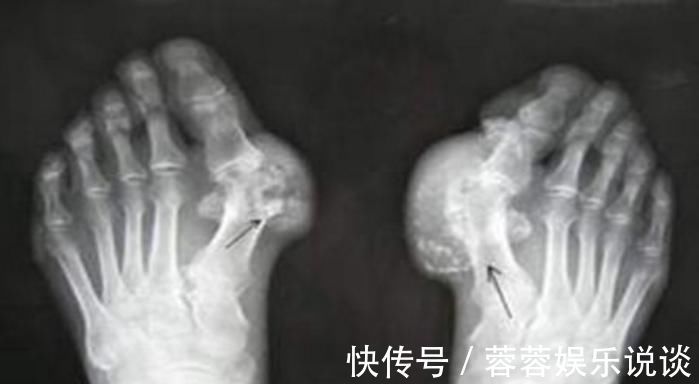

(4)慢性痛风石性痛风:痛风石是尿酸盐结晶沉积在关节内或关节周围组织,逐渐增大,形成突出于皮肤表面的黄白色结节。最后可导致关节变形,影响外观及功能。此时如果再不进行溶酸、排酸,很快就会并发其它更为严重的疾病。